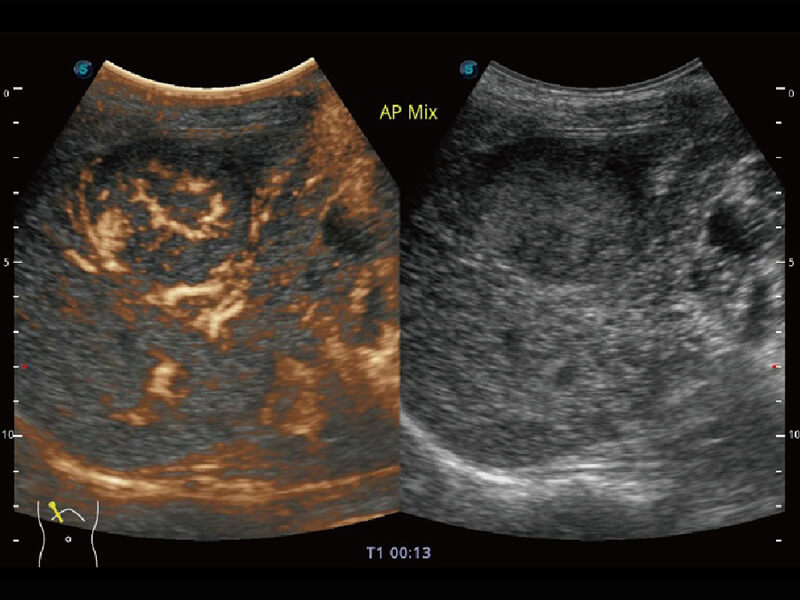

成像功能

S60探头工艺,从前端信号处理每一个环节采集无损声学数据,真实还原组织原貌,再现解剖细节。

超宽频带技术,为容积成像带来优质的二维图像基础,为您呈现丰富的结构细节,栩栩如生地展示宝宝的宫内形态以及各种组织的立体结构。